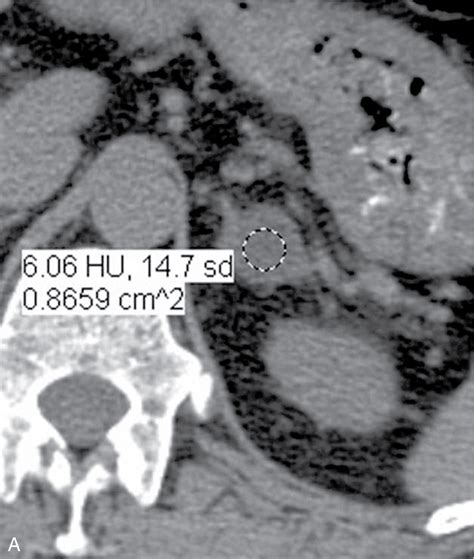

• Imaging Review: A radiologist will analyze the "washout" characteristics of the nodule on a CT scan to estimate the lipid content within the tissue.

Differentiating Between Benign and Malignant Nodules

Differentiating between a harmless adenoma and a malignant tumor is the primary objective of your medical team. Benign adrenal adenomas are the most frequent finding. These are generally small, stable over time, and lipid-rich. Conversely, adrenocortical carcinoma is a rare form of cancer that usually presents as a larger, irregularly shaped mass. Imaging techniques such as contrast-enhanced CT scans, MRI, or even PET scans may be utilized if the initial findings are inconclusive or if the nodule demonstrates suspicious features.